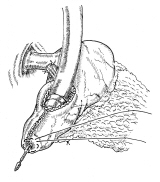

胃全摘術後の再建

器械吻合器を用いた、ρ‐double tract法。